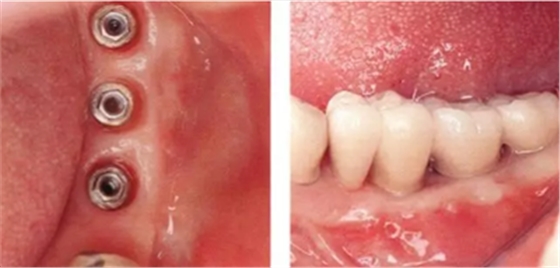

Type2-Class1

的病例(病例3):頰側(cè)的角化齦較少,舌側(cè)到頰側(cè)之間的角化齦寬度在5mm以下,頰側(cè)進行FGG(游離齦移植術(shù))的病例。

▲圖5-1,2

圖5-1 缺損牙槽嵴的角化齦較少,舌側(cè)到頰側(cè)之間的角化齦寬度在5mm以下(Type2-Class1)。

圖5-2 從腭側(cè)采集游離齦移植片,通過FGG(游離齦移植)將其移植到頰側(cè),保留舌側(cè)原有的角化齦。

▲圖5-3,4

圖5-3 第二次手術(shù)時的頰側(cè)面照。進行FGG時,需修整受瓣區(qū),確保移植片不會移動,并且需緊密地縫合、固定移植片。

圖5-4 FGG(游離齦移植)后4個月的頰側(cè)面照。獲得了充足的角化齦。

▲圖5-5,6

圖5-5 同時期的(牙合)面照。舌側(cè)也有充足的角化齦。

圖5-6 佩戴最終修復(fù)體時的頰側(cè)面照。